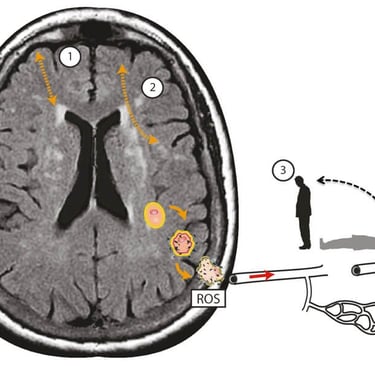

Şekil 1. Kortiko-subkortikal beyin küçük damar hastalığı ile ilişkili baş dönmesinde postüral kan basıncı hipotansiyonunun ek zararlı etkilerinin şematik gösterimi. (1) ve kortiko-kortikal (2) bağlantı kopukluğu. Lokalize oksidatif stres süreçleri serebral damarları hasarlandırarak endotel disfonksiyonuna yol açar ve reaktif oksijen türleri (ROS) yoluyla beyin dokusunda nörodejeneratif değişiklikleri teşvik eder. Mikrovasküler endotel disfonksiyonu ise serebral otoregülasyonu bozar; bu da sağlıklı durumlarda kan basıncı düştüğünde yeterli ve istikrarlı serebral kan akışını korur. Bu, postural baş dönmesi ve dengesizlik olarak kendini gösteren intra-serebral ortostatik hipotansiyon ve perfüzyona yol açar. Kaski ve ark. [4]'den Elsevier'in izniyle yeniden basılmıştır. Bu tür dağıtılmış fonksiyon, aynı anda birçok alanda birden fazla bağlantıyı etkileyen cSVD tarafından bozulma riski altındadır. Yaşla ilişkili serebral küçük damar hastalığının (cSVD) birikimiyle oluşan bağlantı kaybı, aşağıdaki mekanizmalardan bir veya daha fazlası aracılığıyla baş dönmesi hissine yol açabilir (bkz. Şekil 1): kortikal vestibüler merkezlerin bağlantısının kesilmesi, frontal yürüyüş merkezleri ile bazal gangliyonlar arasındaki bağlantının kesilmesi ve amaçlanan motor eylem (efference kopyası) ile yükselen duyusal girdiler (duyusal re-afféference) arasındaki bağlantının kesilmesi. Ek olarak, serebral kan basıncının cSVD aracılı düzensizliğinin ayakta durma ve yürüme sırasında baş dönmesiyle bağlantılı olduğunu ve bu hastalarda kollardaki postural kan basıncı ölçümünün genellikle normal olmasının nedenini açıkladığını öne sürüyoruz [4]. Şu anda, baş dönmesinin net bir nedeni olmadığı için, tedavi hastaların semptomlarını yönetmelerine ve genel olarak dengeyi iyileştirmek için fizyoterapiye odaklanmaktadır. Serebral küçük damar hastalığı ile bağlantı, bu hastalarda yaşa bağlı olarak aşırı beyaz madde hiperintensiteleri veya küçük damar hastalığının diğer belirteçlerinin kanıtlarını aramak için beyin MR'larının istenmesinin faydalı olabileceğini düşündürmektedir. Eğer mevcutsa, sigara, hipertansiyon ve diyabet gibi vasküler risk faktörleri araştırılmalı ve en uygun şekilde ele alınmalıdır. Kronik küçük damar hastalığında (cSVD) optimal kan basıncı, devam eden bir araştırma alanıdır (PROHIBIT-ICH) ve küçük damar hastalığını daha iyi hedefleyen yeni ilaçlar üzerine çalışmalar devam etmektedir (LACI-2).